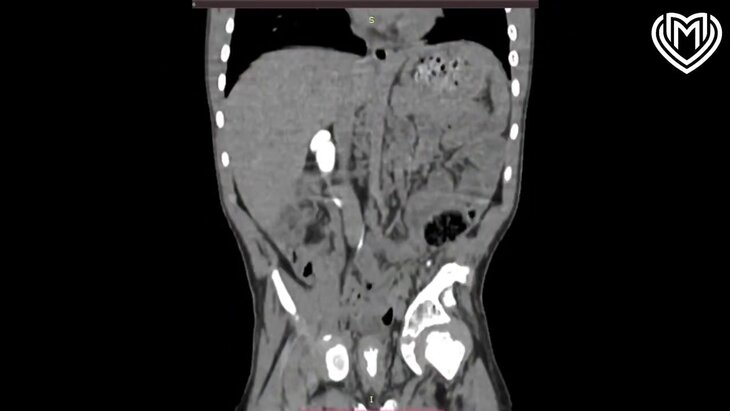

Фото: телеграм-канал "Московская медицина"

Врачи детской городской клинической больницы № 9 имени Г. Н. Сперанского спасли 7-летнего мальчика, который был доставлен в больницу с редкой аномалией – ретрокавальным мочеточником. Об этом сообщает пресс-служба столичного Депздрава.

По данным ведомства, из-за этого врожденного порока мочеточник спиралевидно огибает нижнюю полую вену, что приводит к застою мочи в лоханке и к ухудшению работы почек. При этом детский хирург и уролог-андролог Эдуард Айрян добавил, что ретрокавальный мочеточник может повлиять на нарушение выведения мочи из почки в мочевой пузырь.

"Моча плохо оттекала на двух уровнях: в зоне добавочных сосудов и перекресте с полой веной", – указал Айрян.

Однако врачам разных профилей удалось отсечь мочеточник от лоханки, а после переместить его перед полой веной и ушить. В результате операции хирурги смогли восстановить правильное анатомическое положение органов. Через 10 дней ребенок был выписан домой в хорошем состоянии.